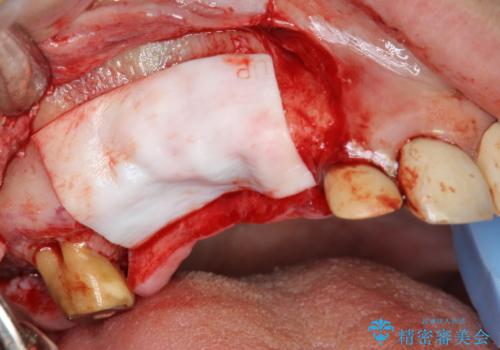

- 120万円(インプラント×3 チタンカスタムアバットメント×3 メタルボンドクラウン×3 骨造成 歯肉移植)費用は治療当時の料金となります

インプラントが長持ちするために、インプラント周囲の十分な骨量・角化歯肉の存在・安定した咬合を一つづつ整備する治療を行いました。